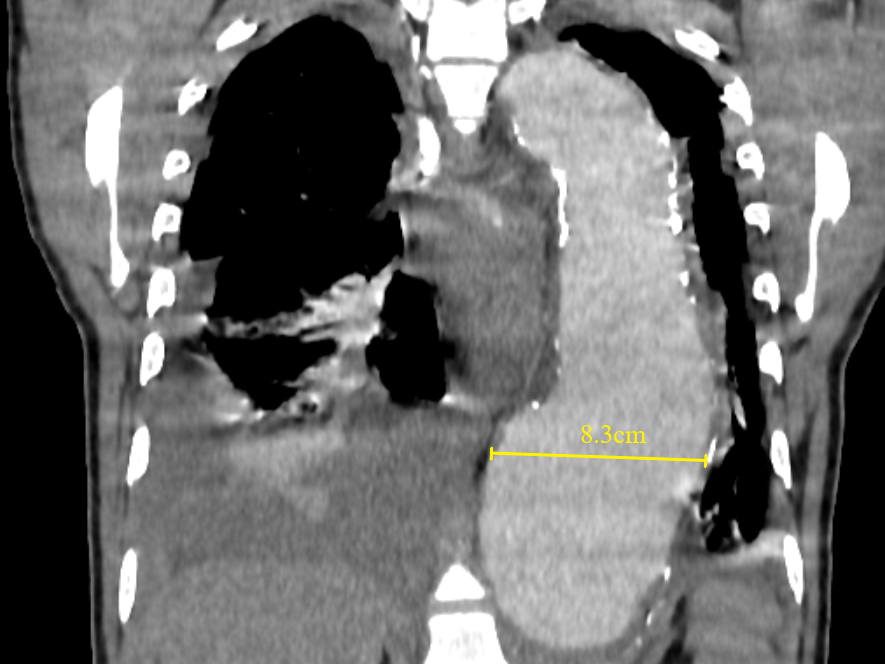

A large baseline aneurysm size, exceeding 7cm (Figure 12) and a rapid size progression of more than 10mm increase per year are associated with a higher risk for rupture.38,40,41 Additional CT findings that are predictors of aortic aneurysm instability include low thrombus-to-lumen ratio, luminal expansion with lysis of thrombus, “hyperattenuating crescent sign”, fissuration of thrombus, periaortic hemorrhage, a penetrating atherosclerotic ulcer, focal discontinuity of intimal calcification (Figure 13), and the “draped aorta sign.38,41 Correct documentation of any pleural effusion, pericardial effusion, or periaortic hematoma is a must as they are associated with increased risk of progression and mortality.42 Primary signs of aortic aneurysm rupture include retroperitoneal hematoma, periaortic fat stranding, and active extravasation of contrast material at the site of rupture.38,43

Figure 12 Coronal contrast-enhanced CT thorax image shows a large thoracic aortic aneurysm (measuring approximately 8.3cm in maximal diameter). Baseline aneurysmal diameter exceeding 7cm is at a higher risk of aortic rupture than smaller aneurysms. Pleural effusions, as seen in this case, must be reported as they are associated with instability and progression.